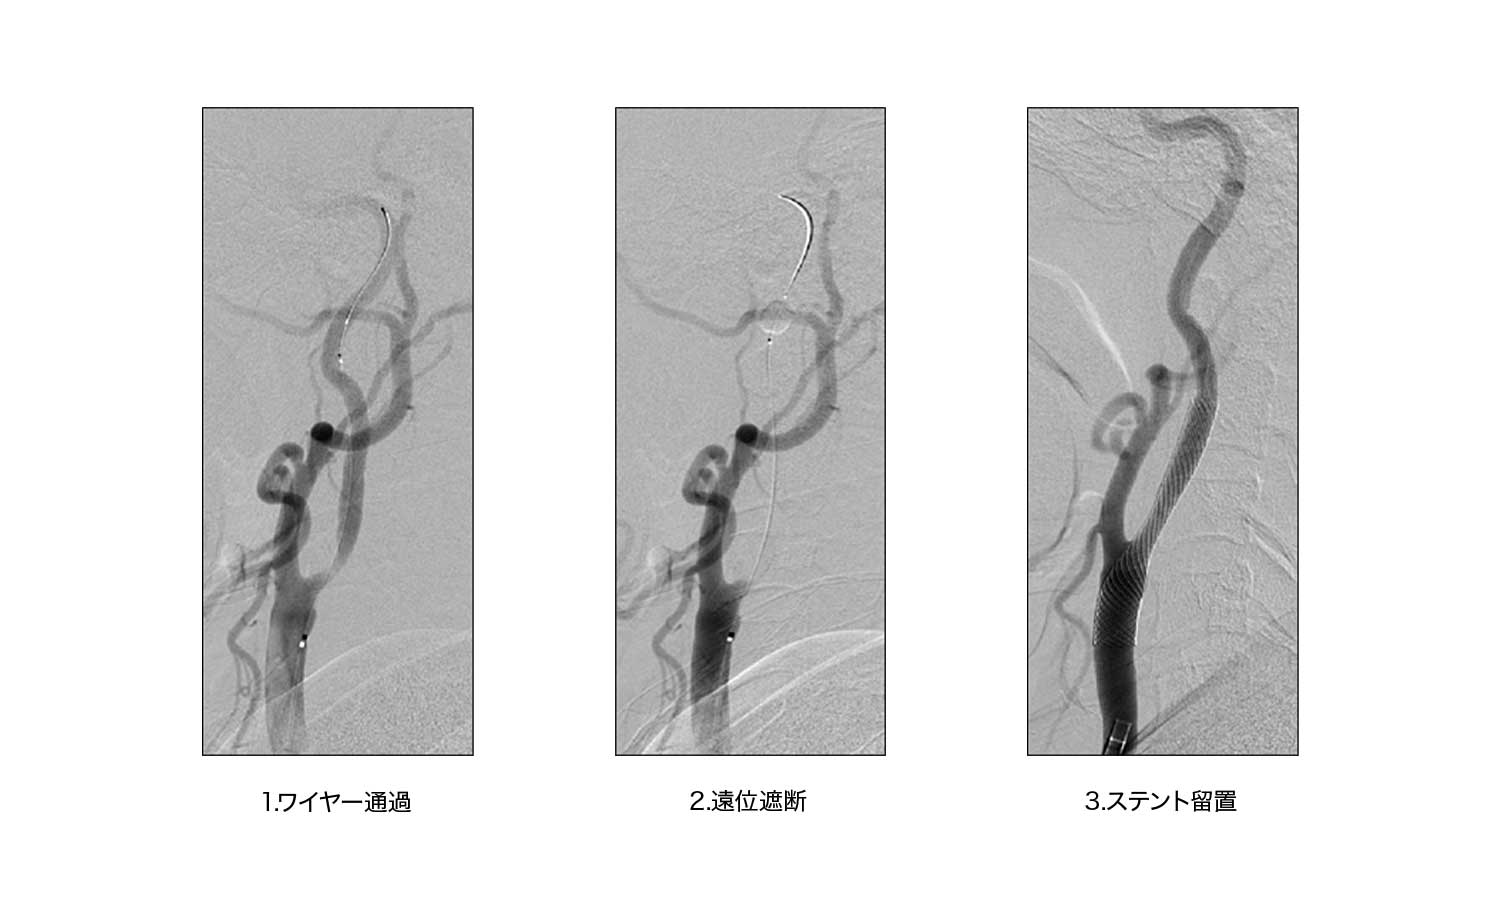

狭窄の程度が強くなると、その後の脳梗塞を予防するために観血的手術である頸動脈内膜剥離術もしくは脳血管内治療である頚動脈ステント留置術が必要となります。高齢化が進み麻酔をかけるリスクが高い患者様に対しては侵襲度の低い頚動脈ステント留置術を積極的に行っております。

頸動脈ステント留置術(CAS)

![]() 1.ワイヤー通過 |

![]() 2.遠位遮断 |

![]() 3.ステント留置 |